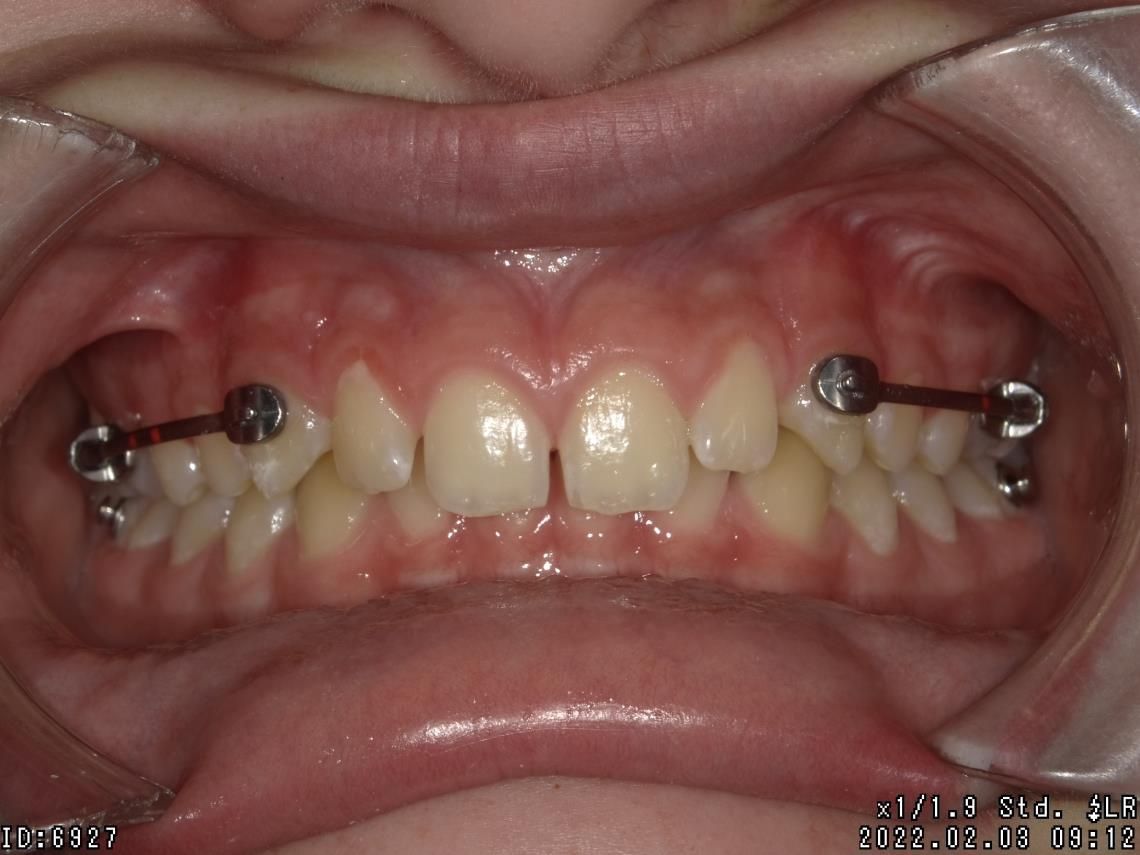

LES BAGUES

Cet appareil dentaire fixe est composé de brackets ou bagues, sortes de petits boutons en métal, en plastique ou en céramique, collés sur les dents et reliés par un fil. Il permet de déplacer les dents du patient dans la direction optimale, de les réaligner au fur et à mesure, de traiter des cas complexes de manque de place et des dents retenues ou dystopiques. Le traitement est moins tributaire de la coopération du patient.